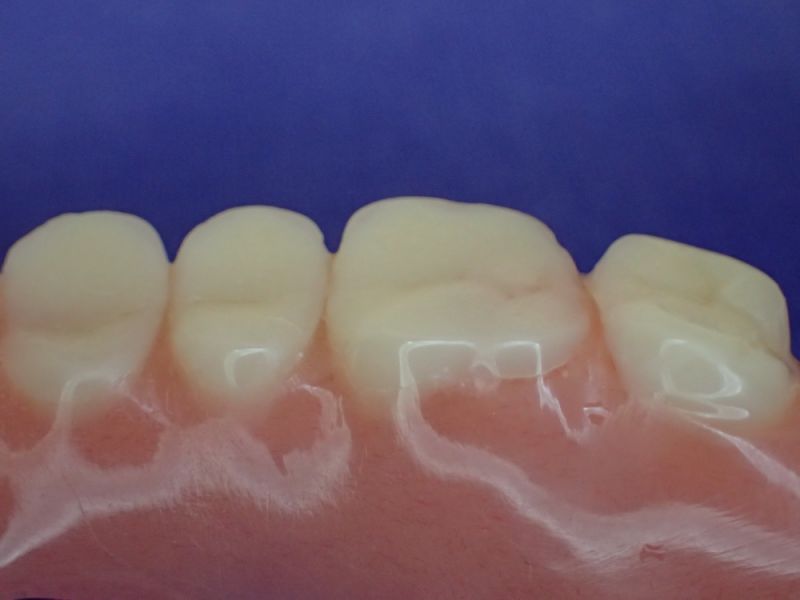

Nach inzwischen 12 jähriger Tragedauer wurden alle Kunststoffteile erneuert, das metallische Grundgeroüst der Arbeit erhalten und die Arbeit befindet sich in einem Zustand, der sich weitgehend an der Ersterstellung orientiert.

Bei derartigen Arbeiten ist es tatsächlich möglich grundlegende Konstruktionsmerkmale einer alten Arbeit zu übernehmen und Verschleißteile aus Kunststoff zu erneuern.

Im Prinzip ist das beliebig oft möglich und für den Patienten mit einer enormen Kostenersparnis verbunden.